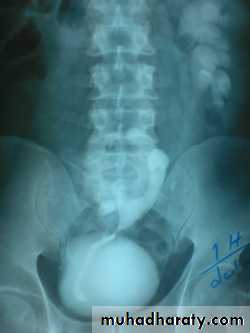

:*Ectopia vesica :-bladder located at low position with separartion of symphysis pubis.